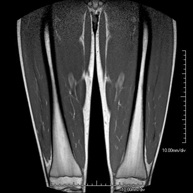

- Thigh MRI

Ideal examination for studying injuries to the hamstrings and quadriceps, which are frequently injured in athletes. It also allows for a good assessment of tendons and peripheral nerves. It lasts approximately 20 minutes. It is a radiation-free procedure.